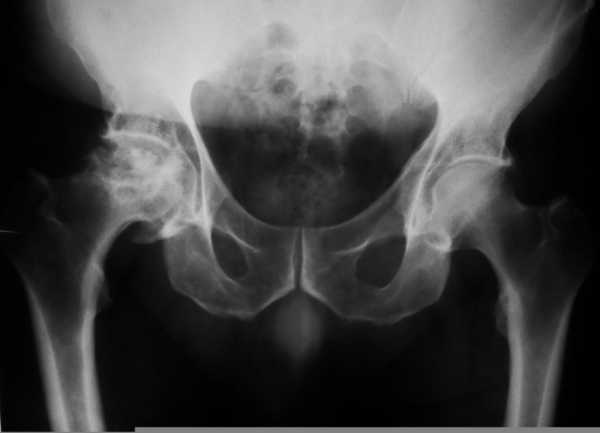

При рентгеновском обследовании просматривается уменьшение суставной щели. Она почти вдвое меньше положенной нормы. Нарушается положение головки бедра, наблюдается разрастание хрящевой ткани. Но эти признаки воочию видны только врачу, поэтому пытаться диагностировать самостоятельно не рекомендуется. Точный диагноз, так же, как и медикаментозное лечение может назначаться исклю

Чтобы диагностировать коксартроз, нужно сделать рентген сустава и описать доктору симптомы, которые беспокоят человека. После физиологического осмотра сустава, врач сможет точно поставить диагноз.